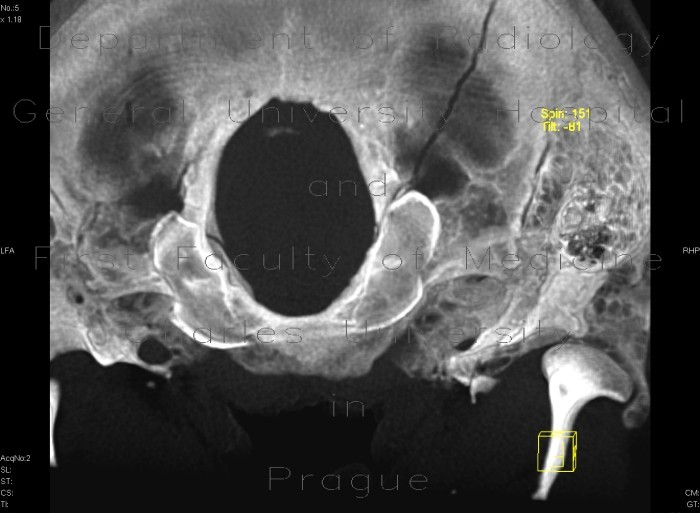

from atlas.mudr.org

Radiology case Fissure of occipital bone, terminating in foramen magnum